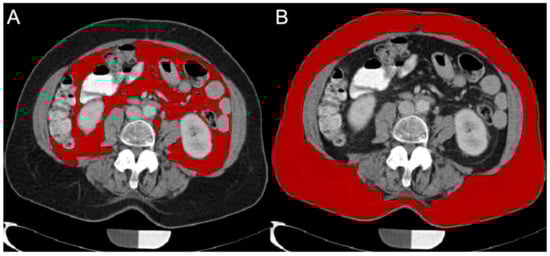

2.4.2. Subcutaneous Adipose Tissue (SAT) and Visceral Adipose Tissue (VAT) Volume Quantification

For SAT and VAT calculations, axial reformations with 5 mm slice thickness were used. Images were loaded in MITK (Medical Imaging Interaction Toolkit; mitk.org). The slice at the level of L4/5 was identified and two adjacent slices cranial and caudal, respectively, were included in the fat volume quantification. These regions were repeatedly used for SAT/VAT quantification in literature and pose standardized localizations for quantitative volumetric assessment [19,26]. SAT-VAT segmentation was performed manually assisted by a region growing based algorithm, operating threshold and pattern based. SAT volume defined as the volume circumscribed by the abdominal cutis as the outer border and the abdominal and paravertebral musculature as the inner border. The VAT volume was identified and quantified according to Sheu et al. [18]. The borders of the local musculature were identified and excluded from the SAT/VAT segmentation. The VAT was defined as the sum of all voxels within the inner border, which were neither muscle nor intestinal tissue and were in the adipose tissue range. SAT was defined as the voxels within the outer and inner border, the tissue from the cutis to the muscle tissue was included (Figure 2). All image analysis steps were performed by a radiologist with three years of experience.

Figure 2. Representative segmentation for visceral adipose tissue (VAT; (A)) and subcutaneous adipose tissue (SAT; (B)) is shown at the level of L4/5.